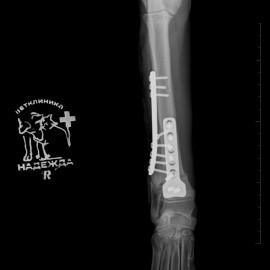

Наш пациент после автотравмы. После осмотра и проведения рентгенологических исследований выл поставлен диагноз - косой диафизарный перелом правой лучевой и локтевой кости со смещением. Была проведена операция - остеосинтез костей правого предплечья.

Снимки после операции.